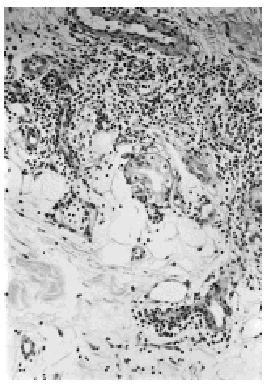

No se encontraron alteraciones en la analítica general ni en el estudio inmunológico, que incluía autoanticuerpos, anticuerpos anticardiolipina, complemento, inmunoglobulinas, factor reumatoide y estudio de crioglobulinas y crioaglutininas. La serología frente a hepatitis fue negativa. El estudio histopatológico reveló un infiltrado inflamatorio perivascular de predominio linfocitario a nivel de dermis superficial y profunda, afectando notablemente la interfase dermohipodérmica y en menor medida el tejido celular subcutáneo en el que el infiltrado aparecía preferentemente a nivel septal (fig. 2). La inmunofluorescencia directa fue negativa.

Fig. 2.--Infiltrado linfocitario en la interfase dermohipodérmica.